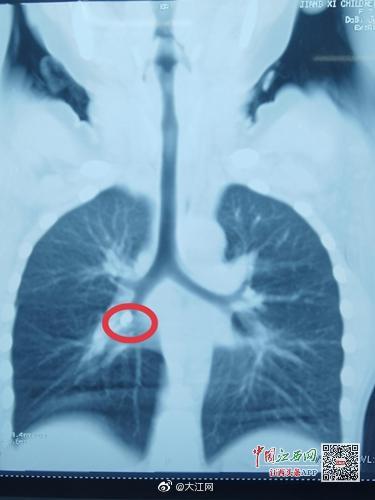

大江快報 【江西7歲男孩咳嗽不止 原來是門牙嗆入了氣管】近日,江西省兒童醫(yī)院接診了一名特殊的患者,7歲的小巖換牙后一直被咳嗽所困擾,怎么治都不見好。經(jīng)檢查,發(fā)現(xiàn)小巖支氣管內(nèi)有異物,醫(yī)生取出后才發(fā)現(xiàn)異物竟然是一顆牙齒。 上饒市橫峰縣的小巖今年7歲了,正是換牙的年齡,兩顆“門牙”已經(jīng)脫落一顆,還有一顆搖搖欲墜。小巖吃東西時候門牙處疼痛不適,家屬心疼不已,和小巖商量把搖搖欲墜的牙齒拔掉。不過,在家屬徒手拔下牙齒后,孩子疼痛難受,哭吵起來,慌忙間家屬手上的牙齒掉到嘴巴里面。小巖當(dāng)即出現(xiàn)劇烈咳嗽、顏面發(fā)紺,家屬給予拍背后逐漸緩解,持續(xù)1分鐘咳嗽緩解。家屬以為是口水嗆了,牙齒被吃進(jìn)肚子內(nèi),未引起重視。